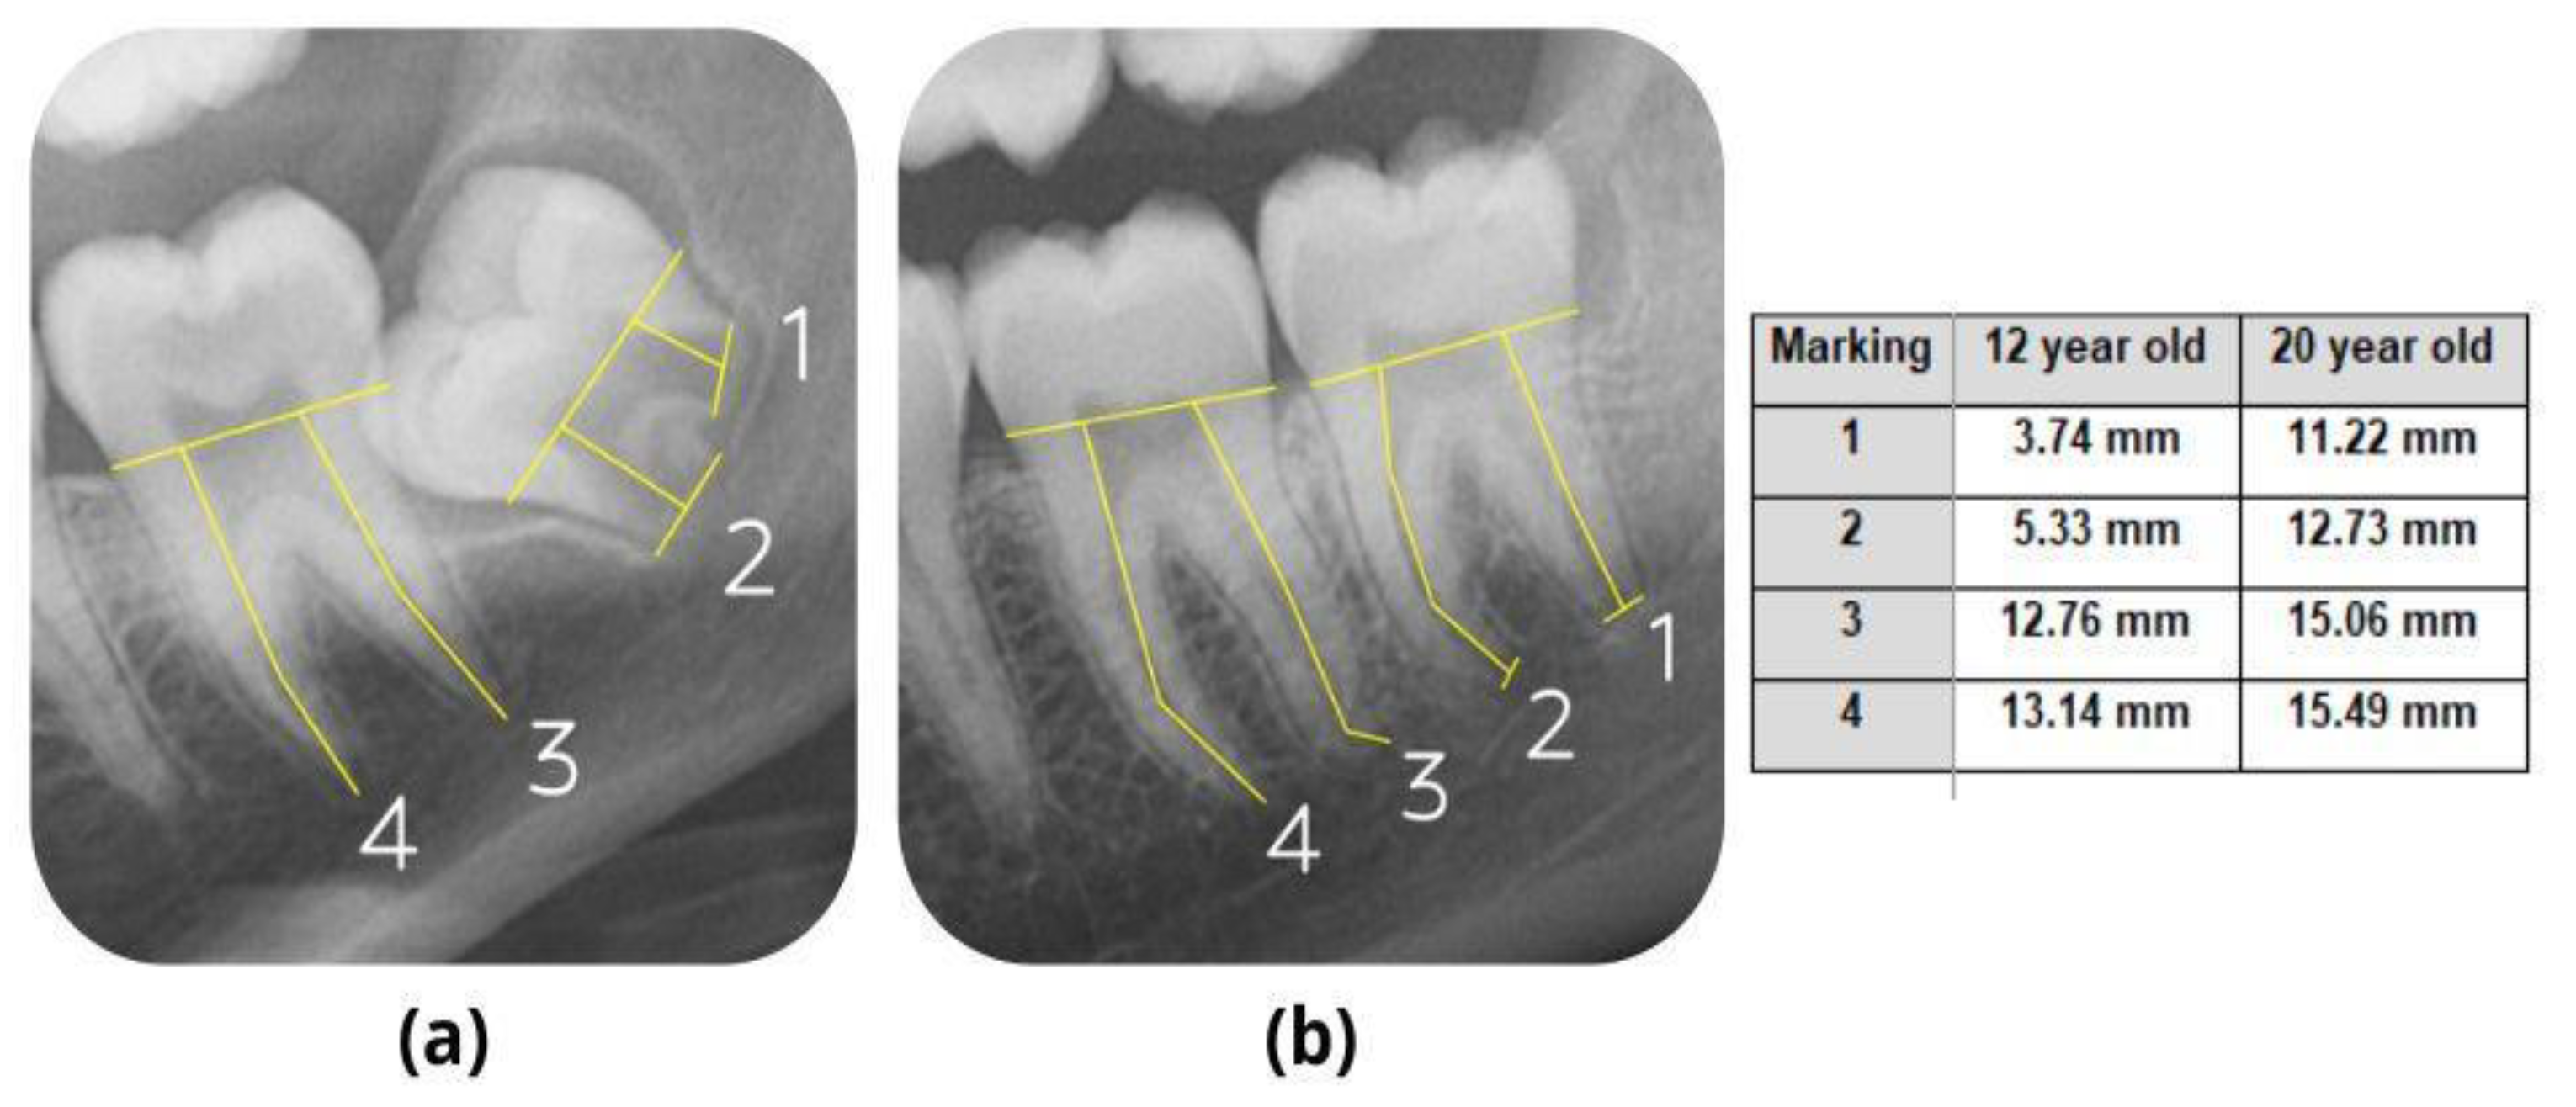

2.2. Measurements